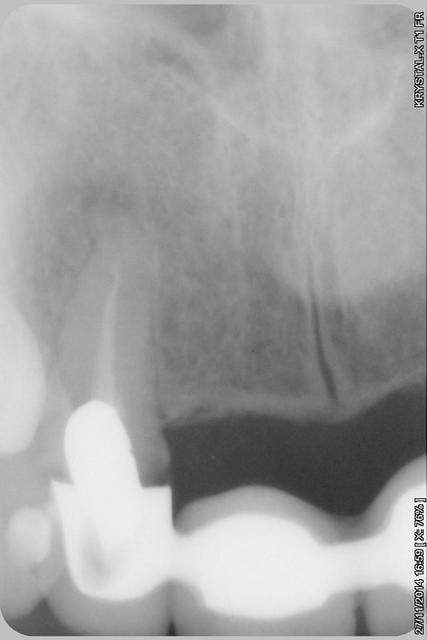

étonnant en effet... et encore plus étonnant, ce qui n'arrive jamais le radiologue (qui est parfaitement compétent normalement) a inversé la droite et la gauche.

le scan n'est pas terrible, mais suffisant pour voir que 22 une fois extraite, ne va pas etre simple à implanter, par contre 11/21 avec un peu d'expansion...

Donc dans un premier temps,je décide d'essayer de retraiter 12/22, de toute façons ça ne peut pas être pire que ce qui tiens depuis 10 ans... enfin 12 mobilité quasiment 3.

Sur la reprise de 22 je pense que tu as fais un beau "tout-droit" à l'apex... le canal devait suivre la courbure.

Tu es bon pour faire une chir-apicale dans quelques mois !

je pense que le tout droit existait déjà..

Oui oui, c'est certain ! il y avait au moins une belle butée bien engagée. Ce qui expliquerai que l'ancien traitement n'allait pas jusqu'à l'apex.

Et avec les instruments de rotation continue agressifs de reprise d'endo que l'on a maintenant, on s'engage dans la butée et on la "termine"... ça m'arrive aussi de temps en temps... de toutes façons, repasser de vieilles butées comme ça, même les endos exclusifs n'y arrivent presque jamais et font une chir apicale d'emblée.